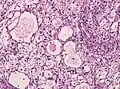

Менинготелиоматозная менингиома состоит из мозаикоподобно расположенных клеток с овальным или округлым ядром, которые содержат умеренное количество хроматина. Строма опухоли представлена немногочисленными сосудами и тонкими тяжами соединительной ткани, которые окаймляют клеточные поля. Характерны концентрические структуры из наслаивающихся одна на другую уплощённых опухолевых клеток. Центр новообразования часто обызвествлён[3].

Фиброзная менингиома состоит из фибробластоподобных клеток, которые располагаются параллельно друг другу и складываются в переплетающиеся между собой пучки, содержащие соединительнотканные волокна. Ядра вытянутые. Могут встречаться концентрические структуры и псаммомные тельца[3].

Переходная менингиома включает элементы менинготелиоматозной и фиброзной менингиом[3].

Псаммоматозная менингиома содержит большое количество псаммомных телец[3].

Ангиоматозная менингиома обильно васкуляризирована, содержит большое количество кровеносных сосудов[7].

Микрокистозная менингиома содержит большое количество микрокист, окружённых опухолевыми клетками звёздчатой формы[8].

Секреторная менингиома является редким гистологическим вариантом данного новообразования. Для неё характерна секреция веществ, которые формируют гиалиновые включения[9].

Менингиомы с обилием лимфоцитов по определению содержат большое количество включений лимфоцитарных масс.

Для метапластических менингиом характерна метаплазия (трансформирование) менинготелиальных клеток в клетки другого типа (к примеру, адипоциты)[10].

Менинготелиоматозная эпендимома

Фиброзная менингиома

Переходная менингиома

Ангиоматозная менингиома

Секреторная менингиома

Папиллярная менингиома

Анапластическая менингиома

Атипическая менингиома

Хордоидная менингиома

Микрокистозная менингиома